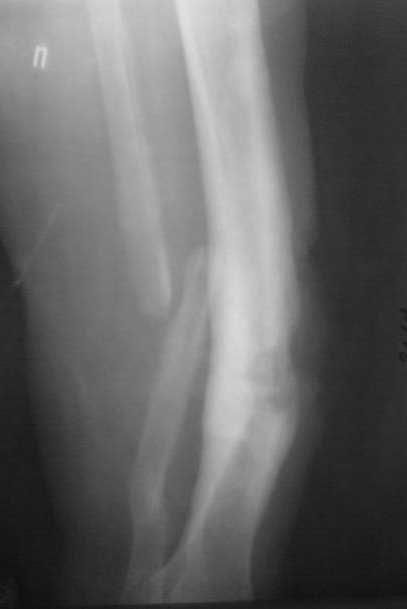

ампутация левой голени на уровне с/3 (опротезирована); открытый перелом с/3 костей правой голени (лечение в аппарате Илизарова). Три года назад появился свищ на передней поверхности голени, лечилась нерегулярно и на сегодняшний момент вот такая картина. Перед госпитализацией, без назначения врача принимала тетрациклин в течение 10 дней.

Взяли посев, заказали дополнительные снимки, перевязка. Правый коленный сустав - движения с полной амплитудой. Частичная нагрузка на правую ногу при ходьбе. Пульсация на a. d. pedis сохранена, стопа теплая. Не температурит. Общее состояние удовлетворительное. Рана с обильным гнойным отделяемым со зловонным запахом на фоне гипергрануляций. Из свища определяю геморрагическое отделяемое.

Снимок месячной давности. Фистулография запланирована на след. неделю.

Планируем: коррекция оси в аппарате, дебридмент, резекция б/берцовой кости с острой копрессией для закрытия полости с бусами из цемента с а/б. Есть гадкое предчувствие, что "вылезет" MRSA на посеве.Надеюсь на помощь в тактике лечения данной пациентки у опытных коллег.